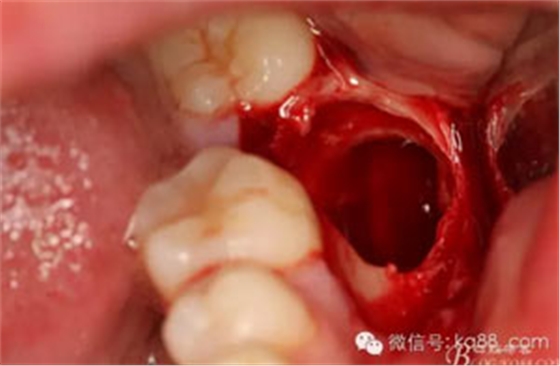

圖15.37拔除后的牙槽窩情況